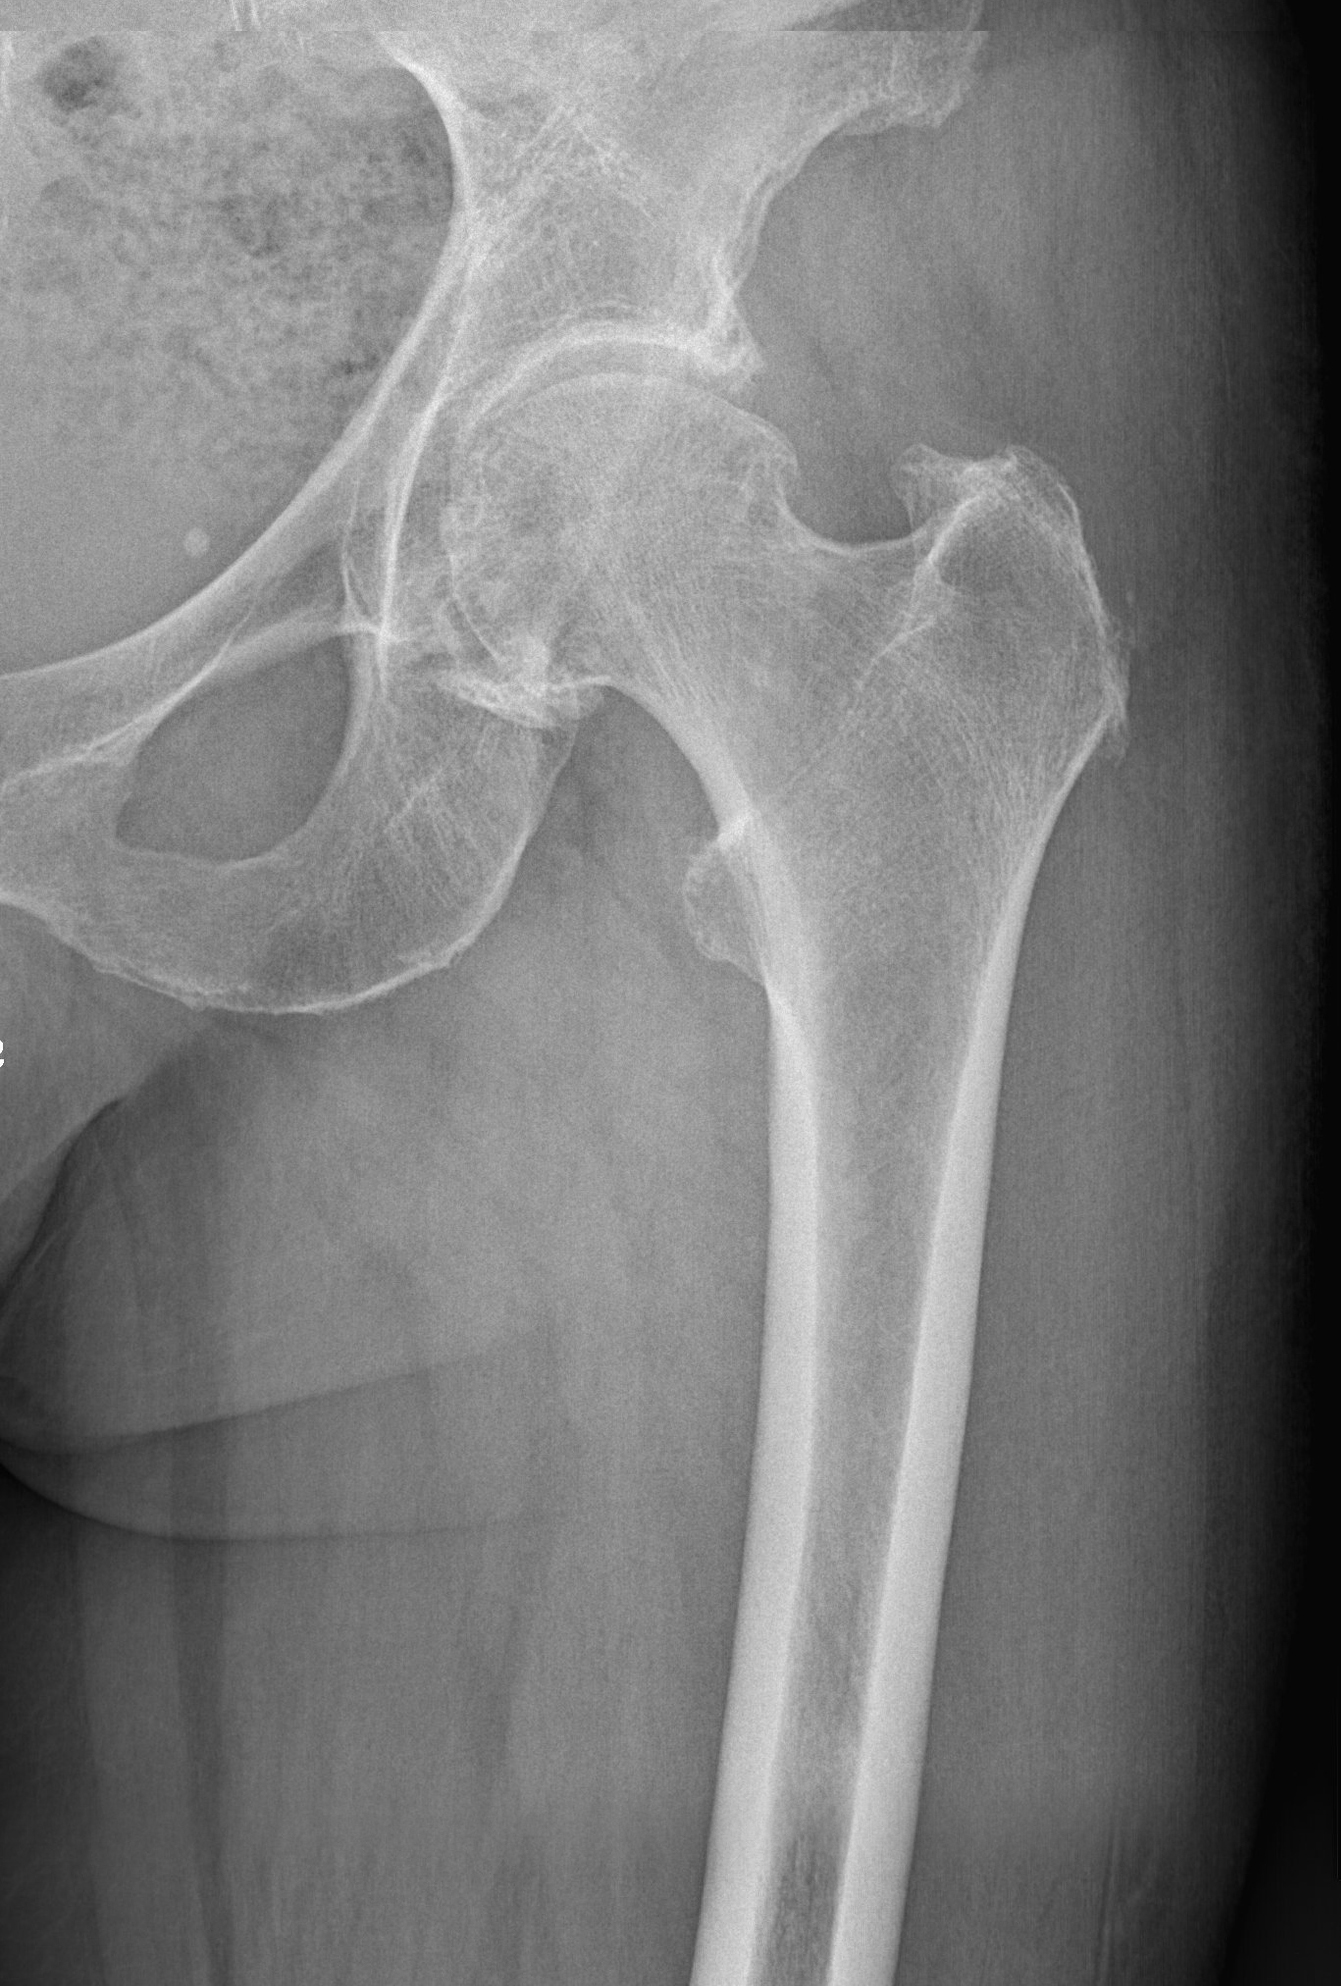

DAS SCHMERZHAFTE HÜFTGELENK:

Die Abnützung des Hüftgelenkes (Arthrose) führt zu immer wieder kehrenden Schmerzen im Bereich des Hüftgelenkes, vor allem im Bereich der Leiste. Durch den Verlust des Knorpels kommt es zur Gelenksentzündung und zu organischen Veränderungen im Gelenk. Als Abwehrmaßnahme des Körpers wird nun durch Knochenanbau versucht, die Bewegung des Gelenkes einzuschränken und dadurch die Entzündungen zu minimieren. Dadurch kommt es allerdings auch zu einer mechanischen Einengung im Gelenk, damit zur Bewegungseinschränkung im Hüftgelenk und wiederum zu Schmerzen.

Dieser Teufelskreis kann nur schwer durchbrochen werden. Die anfangs leichten Schmerzen kommen im Intervall immer häufiger vor und werden stärker. Die Gelenkskapsel kontrahiert sich weiter und die Muskulatur verkürzt sich, die Schmerzen können nun von der Leiste weiter in den vorderen Oberschenkel wandern und rund um das ganze Gelenk auftreten. Nun ist der ideale Zeitpunkt gekommen, um einen Gelenkersatz durchführen zu lassen.